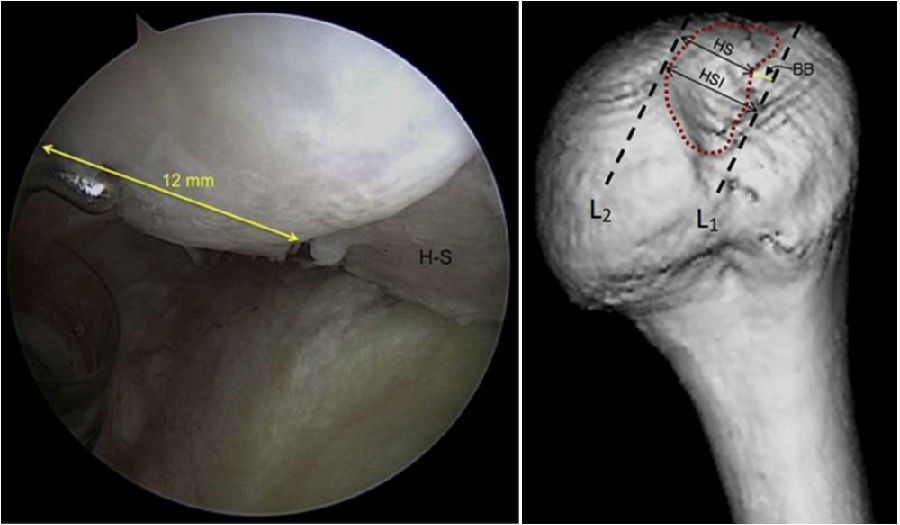

图32 Hill-Sachs损伤测量方式

上图为Hill-Sachs损伤的测量方式,采用前端为4mm的探钩,可以看到Hill-Sachs损伤的区域为3个探钩前端的跨度,因此HS为12mm。

评估报告提示:肩胛盂轨迹(Glenoid Track,GT)19.9mm,Hill-Sachs间距(Hill-Sachs Interval,HSI)24mm。

图34  BB=12

骨桥宽度的测量方式,采用前端为4mm宽的探钩测量,发现骨桥宽度正好为3个探钩前端的跨度,应为12mm。

计算Hill-Sachs间距(Hill-Sachs Interval,HIS)。这个间距应为Hill-Sachs损伤的宽度(HS)加上骨桥(Hill-Sachs损伤的外侧缘到肩袖止点)的宽度(BB),HSI:HS+BB=24mm。